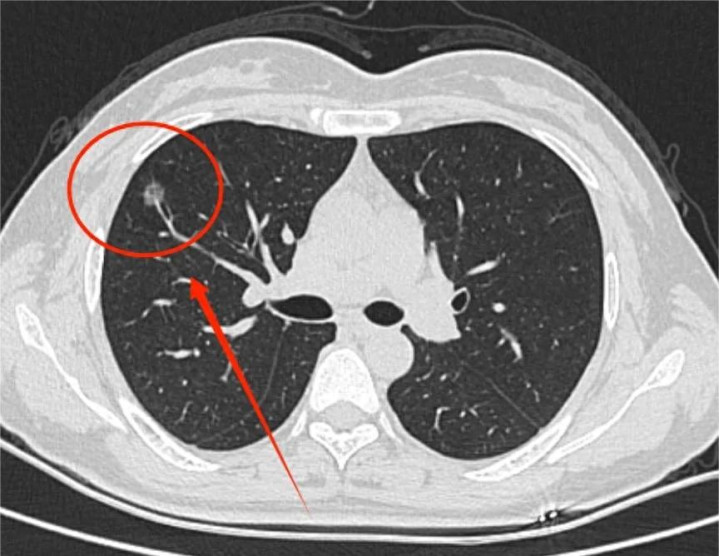

跟着CT期间的精进,“血管穿行”成为肺结节诠释中又一个令东谈主警惕的边幅。它指的是在磨玻璃或羼杂磨玻璃结节里面,昭着可见一支或数支平淡的肺血管穿过,仿佛结节将血管“包裹”或“拽住”。在西医看来,这可能是肿瘤组织分泌促血管生成因子,指引血管协调为其供血,是结节活性较强、滋长可能较快的征兆。

李女士,47岁,2024年1月因偶发胸闷查验,发现左肺上叶有一6mm羼杂磨玻璃结节,CT教唆“其内可见明确血管穿行”。她平时易懆急,口干,月信有血块。舌质紫暗,舌尖红,舌下静脉粗暗怒张,脉细数。

三个月后,李女士胸闷、懆急感大为缓解。复查CT对比:原左肺上叶结节已未见融会!